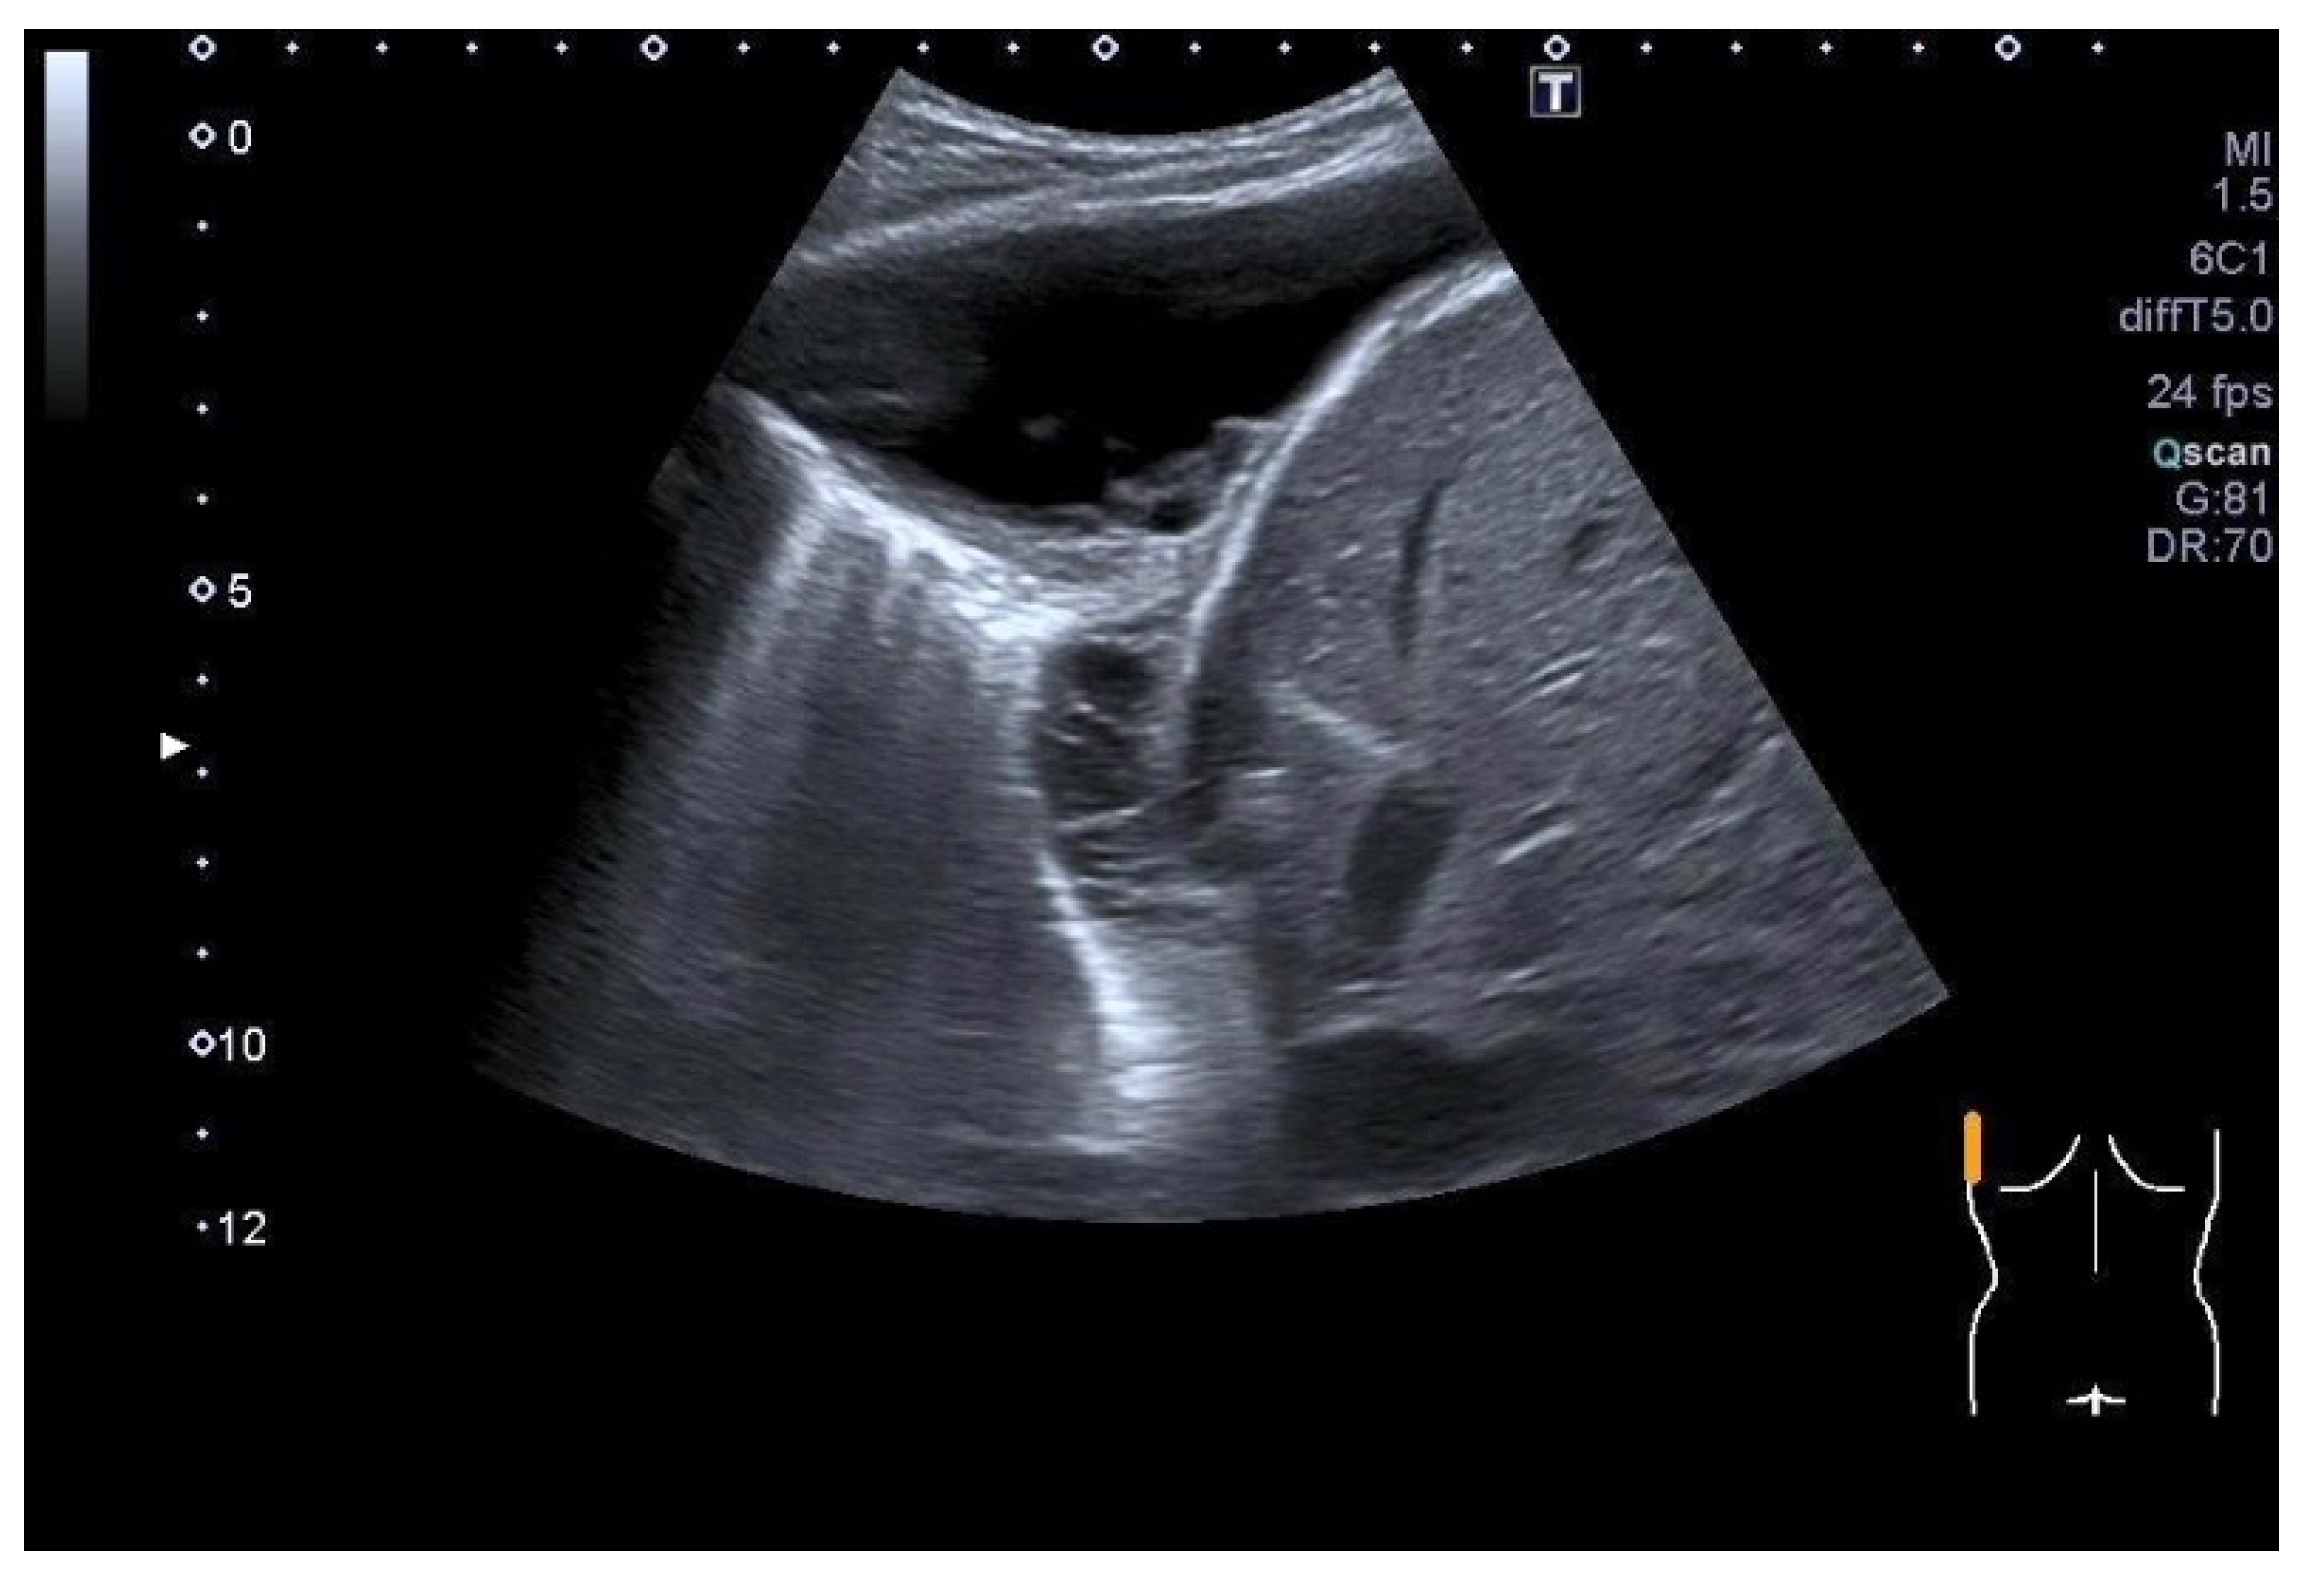

| Splenosis | Round, homogeneous lesions. Macrovessels on CDI are possible. Spleen-typical contrast behavior in CEUS with long-lasting contrast enhancement over several minutes. |